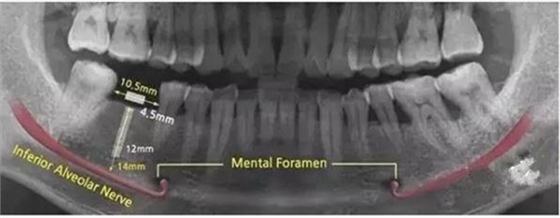

因此治療的第三階段就包括牙周手術(shù)(若需要)和缺牙修復(fù)(包括種植牙)。